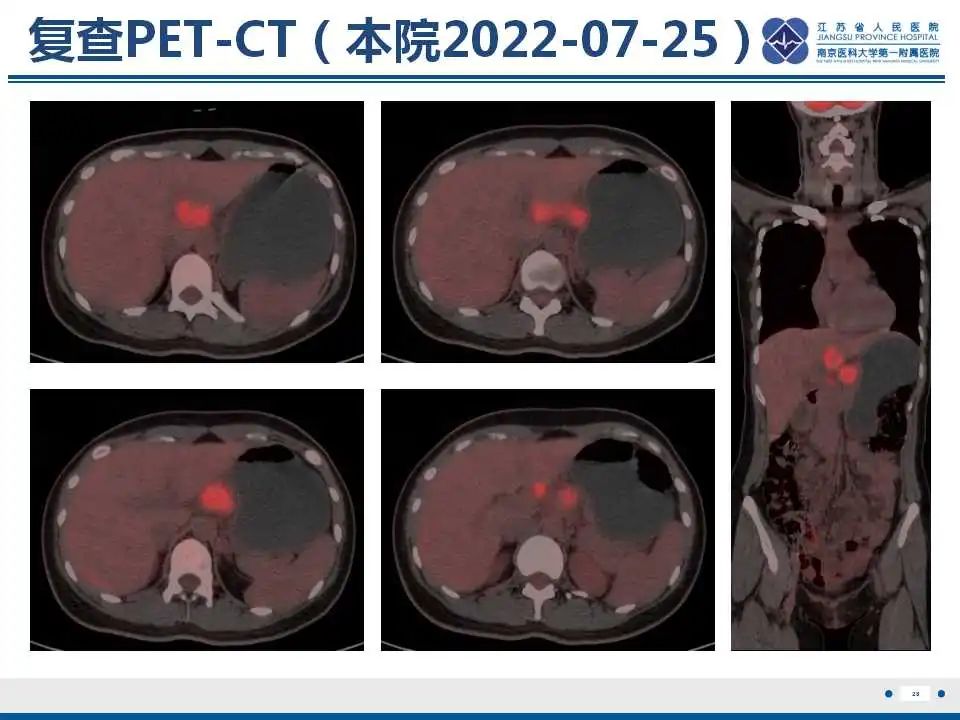

作者:江苏省人民医院 李琼 朱飞鹏

来源:江苏省人民医院放射科